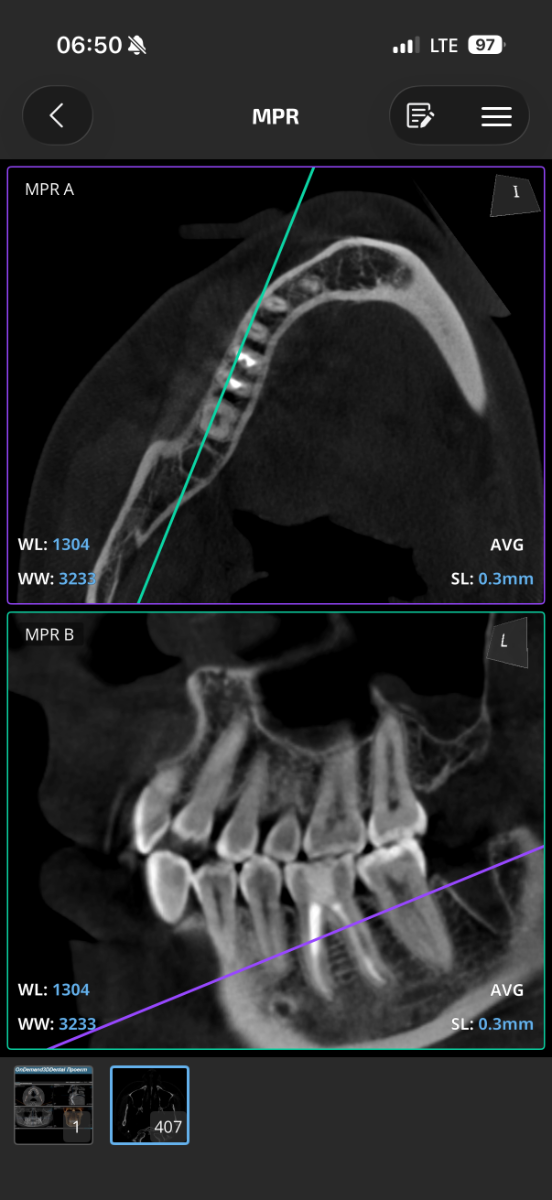

Всем привет, коллеги! 14 лет, терапевты ставят трещину по КТ (снимков до, к сожалению нет, косяк, каюсь). чуть сепарировав зуб и глянув на зуб под отлетевшим куском пломбы трещина "подтвердилась". Кейс на фото. Из интересного - маленький реколл в 1.5 года и спокойное перемещение зуба брекетами!